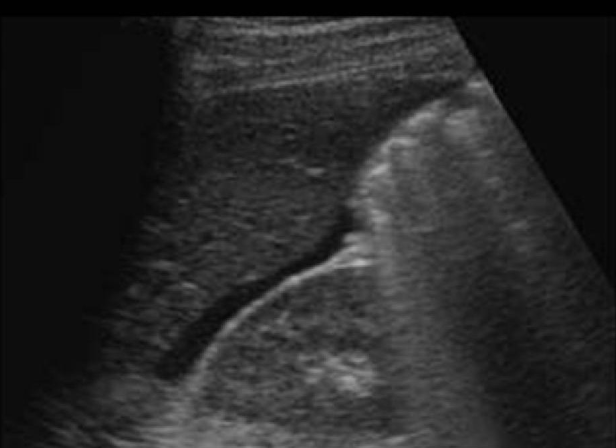

pt has pain + bloating. she has hx of GI tract carcinoma. which is the most likely sono finding in pelvis

a) lymphadenopathy + bilateral ovarian cyst formation

b) krukenberg tumor or ovary + peritoneal cysts

c) lymphadenopathy + krukenberg tumor of ovary

d) lymphadenpathy + brenner tumor of ovary